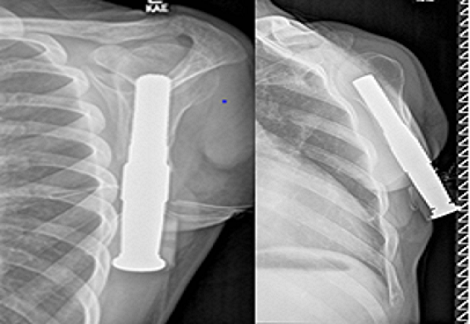

Σε πρώτη φάση ένα στέλεχος από κράμα μετάλλων εμφυτεύθηκε στο οστό το οποίο, αφού ενσωματώθηκε, αποτέλεσε τη βάση για να συνδεθεί ένα εξωτερικό διαδερμικό μέλος. Το τεχνητό χέρι μπορεί πλέον να προστίθεται ή να αφαιρείται με άνεση από το διαδερμικό μέλος. Μετά από μετεγχειρητική νοσηλεία μόλις 7 ημερών, ο νέος εξήλθε από την κλινική απόλυτα ικανοποιημένος δηλώνοντας ότι «το αισθάνομαι σαν το χέρι μου τώρα». Πράγματι, η μέθοδος έχει σχεδιαστεί προκειμένου ο ασθενής, πέρα από τη βελτίωση της κίνησης, να ανακτά την αντίληψη του ίδιου του χεριού του.